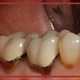

آیا عصب کشی و درمان ریشه دندان در دوران بارداری ممکن است؟

بارداری باعث عفونت نمیشود، اما شما را مستعد ابتلا به عفونت میکند. بنابراین اگر از قبل دندان خراب داشته باشید، بارداری وضعیت شما را بدتر میکند. درمان فوری برای مشکلات تهاجمی دندان، ضروری است. عصب کشی در دوران بارداری هم به عنوان یکی از مشکلات جدی دندان، باید فورا درمان شود.

در هر مرحله از بارداری که هستید نباید درمان خود را به تاخیر بیندازید. در غیر این صورت ممکن است پس از زایمان، باکتریهای عامل پوسیدگی دندان را به کودک خود منتقل کنید. عوارض عدم درمان عفونت دندان به میزان و شدت عفونت بستگی دارد. درست است که عفونت بیشتر در ریشه و بافتهای عصبی دندان ایجاد میشود، اما ممکن است در لثه هم عفونت را ایجاد کند. عفونت لثه هم با وارد شدن به جریان خون، سلامت جنین را در معرض خطر قرار میدهد.

درمان ریشه دندان در دوران بارداری و خطرات احتمالی

عصب کشی یکی از اقدامات ضروری برای حفظ سلامت دندانها است که اگر در بارداری انجام شود، هیچ خطری برای مادر و جنین ندارد. درمان ریشه در بارداری تحت تاثیر موارد خاصی ممکن است خطرناک باشد. در ادامه مهمترین خطرات احتمالی درمان ریشه در بارداری را بررسی میکنیم.